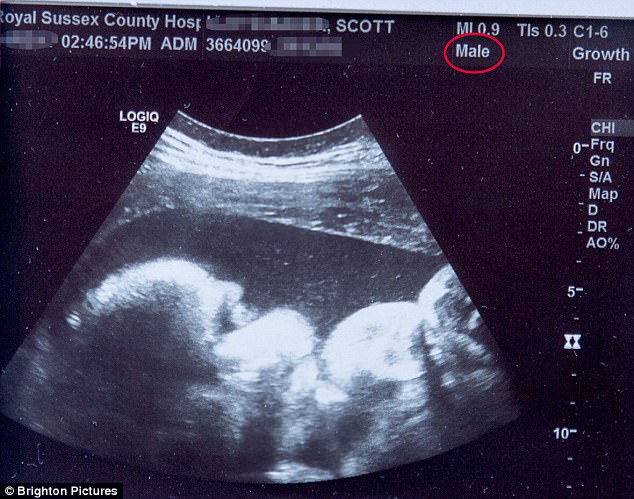

Επίσης στη Βρετανία, στις 29-4-17 -περίπου 7 βδομάδες πριν να γεννήσει ο Hayden Cross το κοριτσάκι του- ο 23χρονος γραφίστας Scott Parker έγινε ο πρώτος άνδρας στη Βρετανία που γέννησε ένα μωρό (ένα κοριτσάκι που ονομάστηκε Sara) στο Royal Sussex County Hospital. Το ιατρικό προσωπικό του νοσοκομείου τον υποδέχθηκε θαυμάσια και τον αποδέχθηκε απόλυτα ως τρανσέξουαλ άτομο.

ο Scott έζησε σαν άνδρας για δύο χρόνια και είναι ένας ασθενής στην κλινική για αλλαγή φύλου (gender identity clinic) στο Νοσοκομείο Charing Cross, στο Δυτικό Λονδίνο, αλλά ανέβαλε την ορμονική του θεραπεία για να γεννήσει τη Sara. Μετά τη γέννησή της άρχισε πάλι να ζει σαν άνδρας και συνεχίζει τη θεραπεία του. Το επόμενο έτος σχεδιάζει να υποβληθεί σε χειρουργική επέμβαση για την αφαίρεση του στήθους του, ενώ περισσότερες χειρουργικές επεμβάσεις θα χρειαστούν για τη μετατροπή και άλλων οργάνων (το κόστος της διαδικασίας για το εθνικό σύστημα υγείας, NHS -χρηματοδότηση από φορολογούμενους- κοστίζει κατά μέσο όρο £ 29.000.)

Ο Scott δεν σκόπευε να μείνει έγκυος, αλλά ανακάλυψε ότι περίμενε παιδί, μετά από ένα μεθυσμένο one-night stand με έναν αρσενικό φίλο του, τον Αύγουστο του περασμένου έτους.

έχει έναν σύντροφο που γεννήθηκε επίσης γυναίκα και κάνει αλλαγή φύλου για να γίνει άνδρας. Σκοπεύει να υιοθετήσει τη Sara και να γίνει νόμιμος γονέας της. Το ζευγάρι είπε ότι ο βιολογικός πατέρας δεν θέλει να εμπλακεί στη ζωή του μωρού.

Ο Scott είπε ότι η απρογραμμάτιστη εγκυμοσύνη του, ήταν η τέλεια ευκαιρία για αυτόν να αποκτήσει ένα παιδί, πριν από την ολοκλήρωση της αλλαγής του φύλου του.